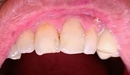

コンポジットレジンは、虫歯の治療を行う際に用いられるプラスチック系の樹脂で、歯の色にぴったりと合うため、目立たず自然な仕上がりになります。特に前歯など、目に見える部分の治療には最適です。また、治療中に歯を大きく削る必要がなく、できるだけ健康な歯を残すことができるため、歯の機能を保ちながら美しい仕上がりを実現できます。

コンポジットレジンとは、虫歯治療や歯の修復に用いられる歯科用材料の一つで、プラスチック系の樹脂を基にした材料です。歯の色に近い色合いのものを使用するため、見た目が自然で目立ちにくく、特に前歯など見える部分の治療に最適です。虫歯の部分を削り、その空間にコンポジットレジンを詰めることで、歯の機能回復と美しさの両方を提供します。

見た目の自然さと耐久性がもたらす利点

コンポジットレジンは、特に前歯の修復に適した材料です。虫歯治療後に目立たず、自然な仕上がりを求める患者に最適です。人前での笑顔や会話で歯を気にすることが少なくなるため、自信を持って生活できるようになります。